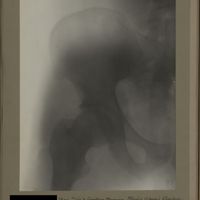

0190 - Page 78 - [Radiographies de la hanche]0190 - Page 78 - [Radiographies de la hanche]